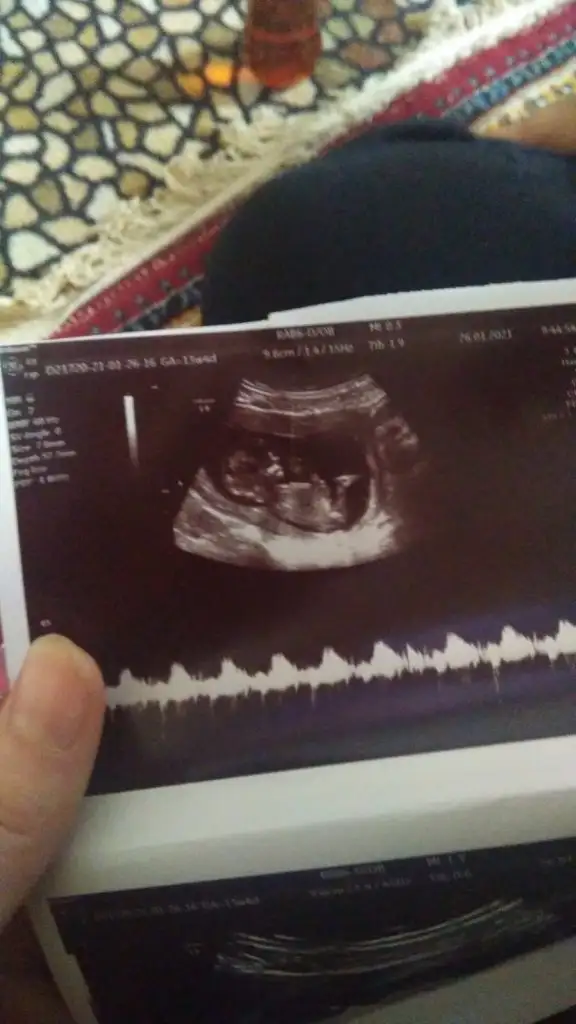

Bende bir kaç kişi diye baktırdım yorumları aynı bakalım sen ne diyeceksin kızkardeşimin 13 haftalık

13 haftalık doktor cinsiyeti söylemedi ama başkalarından tshmin aldim aynı cinsiyet i dediler bebek kardeşimin

Eklentiler

• IMG-20210126-WA0000.webp

20,2 KB · Görüntüleme: 852

• IMG-20210126-WA0002.webp

23,5 KB · Görüntüleme: 683

• IMG-20210126-WA0003.webp

18,7 KB · Görüntüleme: 666